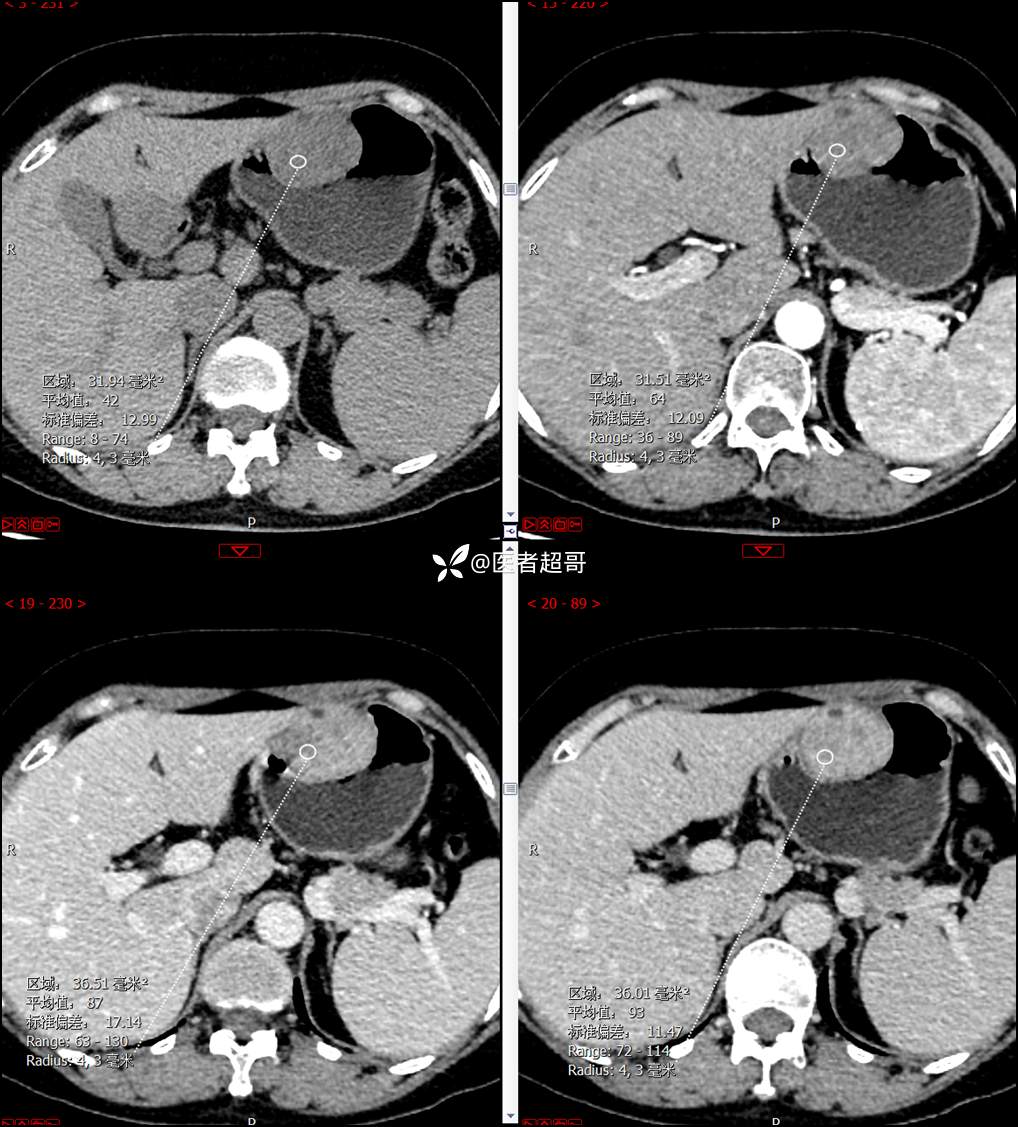

【影诊笔记759】胃体巨大隆起,间质瘤?神经鞘瘤?平滑肌瘤?请鉴别诊断!有结果!

患者半月前无明显原因及诱因出现上腹部疼痛不适,以夜间腹痛为主,无放射性疼痛,间断嗳气,无反酸烧心,无腹泻黑便,于我院门诊行胃镜显示:胃体前壁巨大隆起型病变。